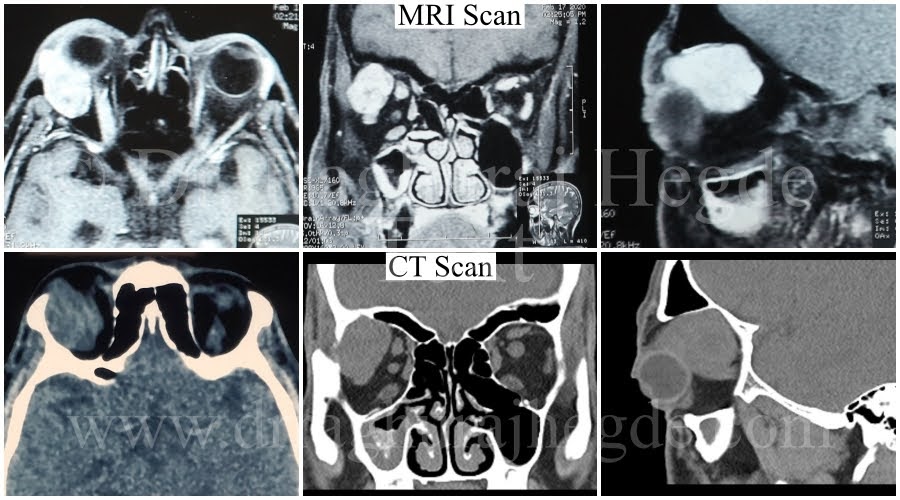

A gentleman came to the clinic with complaints of long standing protrusion of the eye and who had developed double vision a few months back. His scans revealed a lacrimal gland (gland producing tears) mass which was eroding bone in the right orbit pushing the eyeball forward (Proptosis).

The MRI and CT images shows the size of the mass as well as the bone around the mass has eroded.